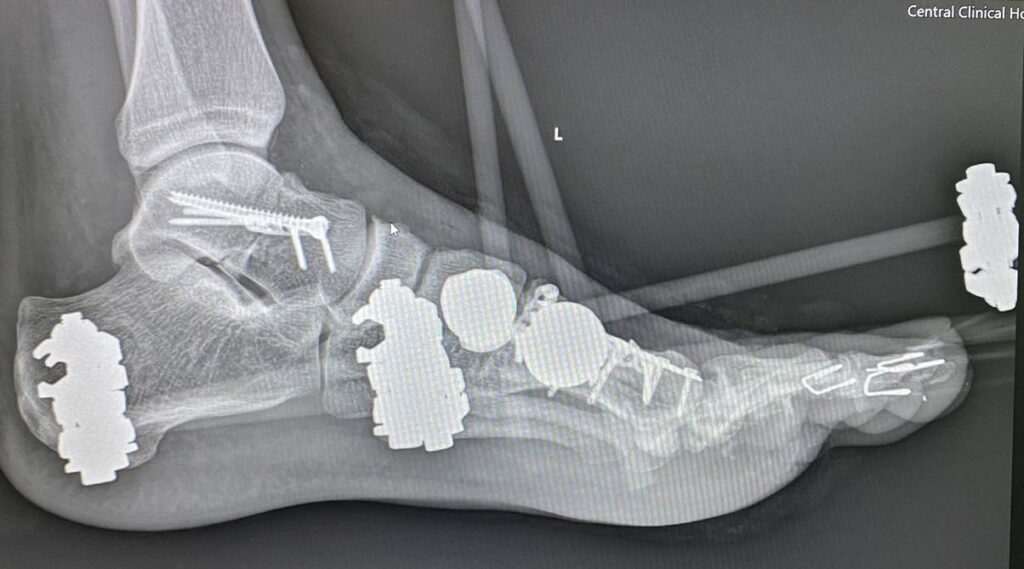

Petro Nikitin:

Наслідки скиду з дрона…

Хірургія стопи сьогодення (…це вам не Халюкси оперувати)

Дякую хірургу Степану Барабашу за чудову роботу